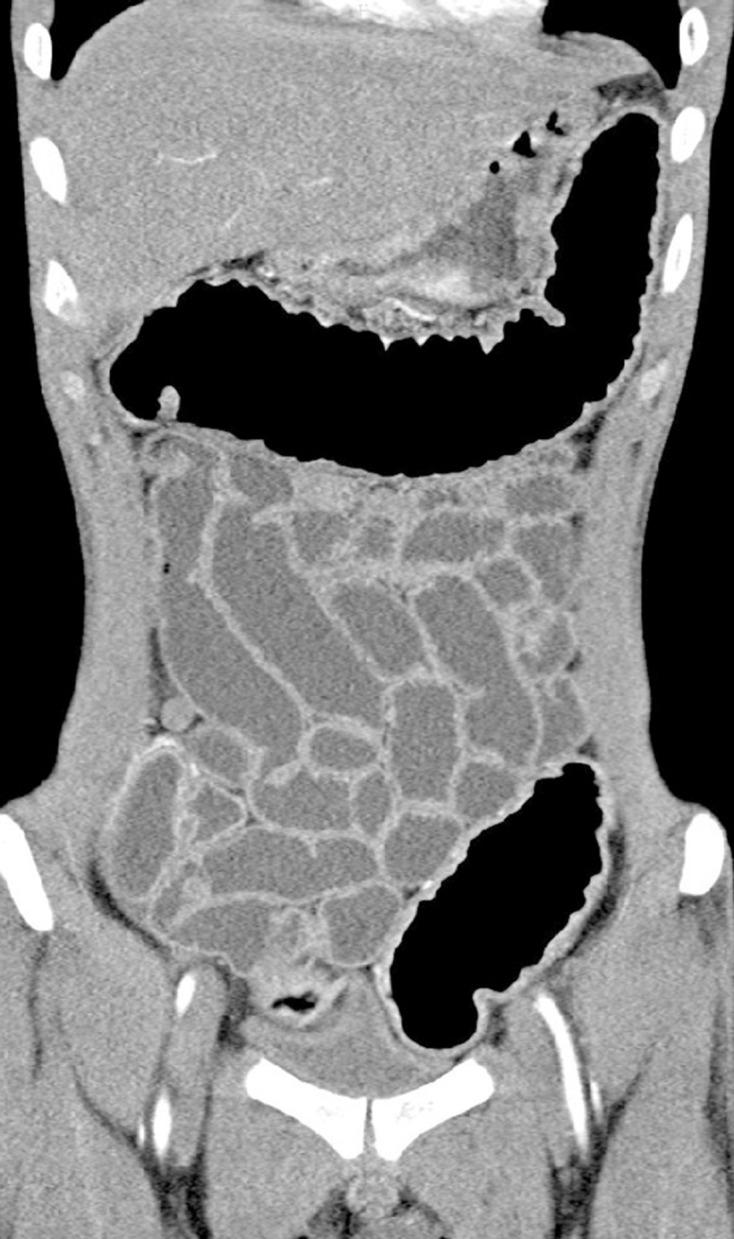

Ulcerative colitis with mucosal lesions in duodenum: Two case reports.

Medicine (Baltimore). 2019 Apr;98(14):e15035. doi: 10.1097/MD.0000000000015035.

Ulcerative colitis with gastric and duodenal involvement.

Rev Esp Enferm Dig. 2017 Jul;109(7):535-536. doi: 10.17235/reed.2017.4685/2016.